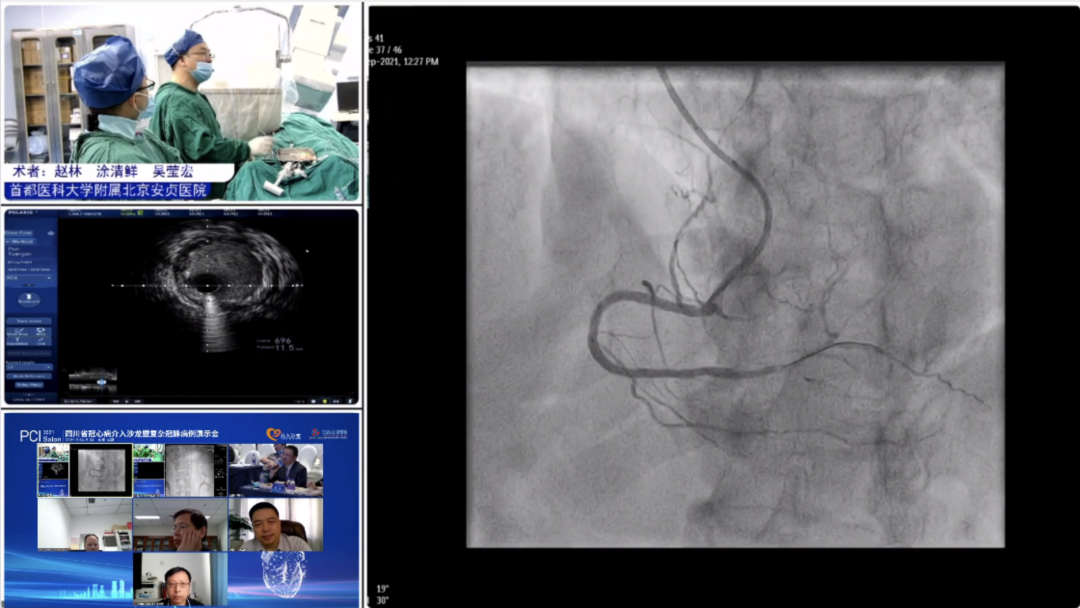

9月25日,大会隆重开幕,大会执行主席、四川大学华西医院贺勇教授主持,大会创始人及名誉主席、四川大学华西医院心内科黄德嘉教授,北京力生心血管健康基金会管廷瑞理事长,大会主席、四川大学华西医院陈茂教授,大会创始人及名誉主席东莞康华医院贾国良教授等多位专家领导分别以线上、线下参会形式共同出席开幕式,并为大会开幕致辞。随后,来自全国多地的冠脉领域资深术者通力配合,带来了11场极具难度和技巧的复杂冠脉病例手术演示及微课讲座。同期进行的护理及技术人员论坛、冠脉腔内影像与生理学论坛、冠心病诊疗论坛、降脂治疗论坛&心衰药物进展论坛、血栓抽吸、药物球囊、愈合型支架等专题学术内容应接不暇、精彩纷呈。